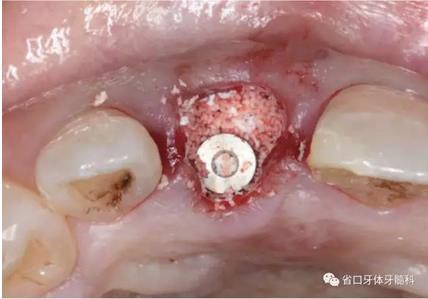

圖16 跳躍間隙植骨

圖17 跳躍間隙植骨

(1)微創(chuàng)拔牙及即刻種植:術(shù)前拍攝口內(nèi)照及實(shí)施牙周基礎(chǔ)治療。常 規(guī)消毒鋪巾阿替卡因局麻下微創(chuàng)拔除上頜右側(cè)中切牙,搔刮拔牙窩及根尖肉 芽組織。探測(cè)牙槽骨唇側(cè)骨壁及鄰面牙槽嵴完整,牙齦無(wú)撕裂。不翻瓣下于上頜右側(cè)中切牙缺隙近遠(yuǎn)中中點(diǎn)的腭側(cè)牙槽骨及根方定位,按照逐級(jí)預(yù)備的原則,緊貼牙槽窩腭側(cè)骨壁制備種植窩洞,植入Zimer®3.7mm×13mm TSV種植體1顆,植入扭矩>35N·cm,以O(shè)sstell測(cè)量種植體的ISQ值為68。 種植體平臺(tái)位于唇側(cè)齦緣中點(diǎn)下3mm,與唇側(cè)骨壁內(nèi)側(cè)面形成的跳躍間 隙約2mm,置入Bio-Oss®細(xì)顆粒骨粉0.25g,上愈合基臺(tái)關(guān)閉創(chuàng)口。術(shù)后 CBCT檢查顯示:種植體利用牙槽窩根方骨質(zhì)固位,緊貼牙槽窩腭側(cè)骨壁, 其唇側(cè)面與牙槽窩唇側(cè)骨壁的內(nèi)側(cè)面所形成的跳躍間隙(約2mm)可見(jiàn)顆 粒狀顯影物充填。牙槽窩的唇側(cè)骨壁及唇側(cè)倒凹無(wú)缺損穿孔。